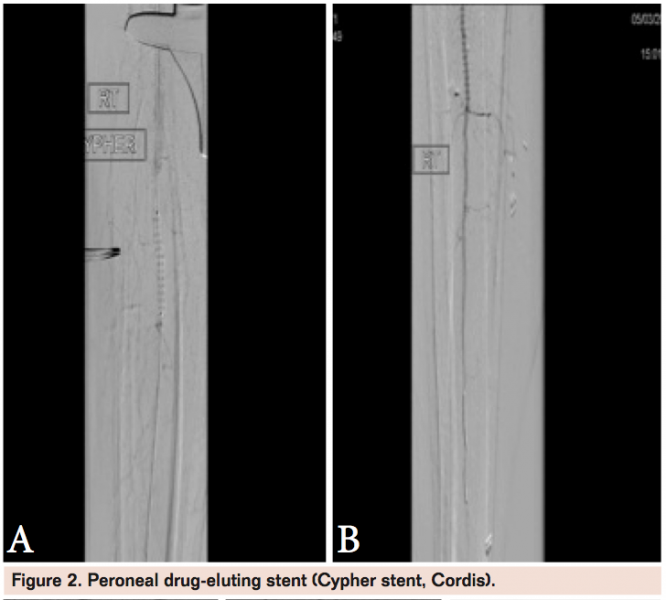

Our patient was initially treated with a small balloon after the lesion in the peroneal was crossed and intraluminal catheter position was confirmed (Figure 1). A pressure wire was placed through the catheter prior to balloon angioplasty. The completion angiogram revealed significantly improved flow without dissection. However, there was a residual Pd/Pa (pressure distal/pressure aortic) of <0.9 so we placed a short drug-eluting stent (DES) in an area of focal residual stenosis (Figure 2). The patient’s ulcer healed and he is currently on clopidogrel for maintenance.

DES have gained popularity in the tibial arteries with a proven track record in small caliber coronary vessels that are similar in caliber to the tibial vessels. Multiple trials have shown diminished amputation rate and target lesion revascularization with follow-up length ranging from 6 months to 3 years. A recent review article by Feiring outlines the available literature on below-the-knee DES technology.9 Drug-coated balloons and bioabsorbable stents are exciting technologies on the horizon.